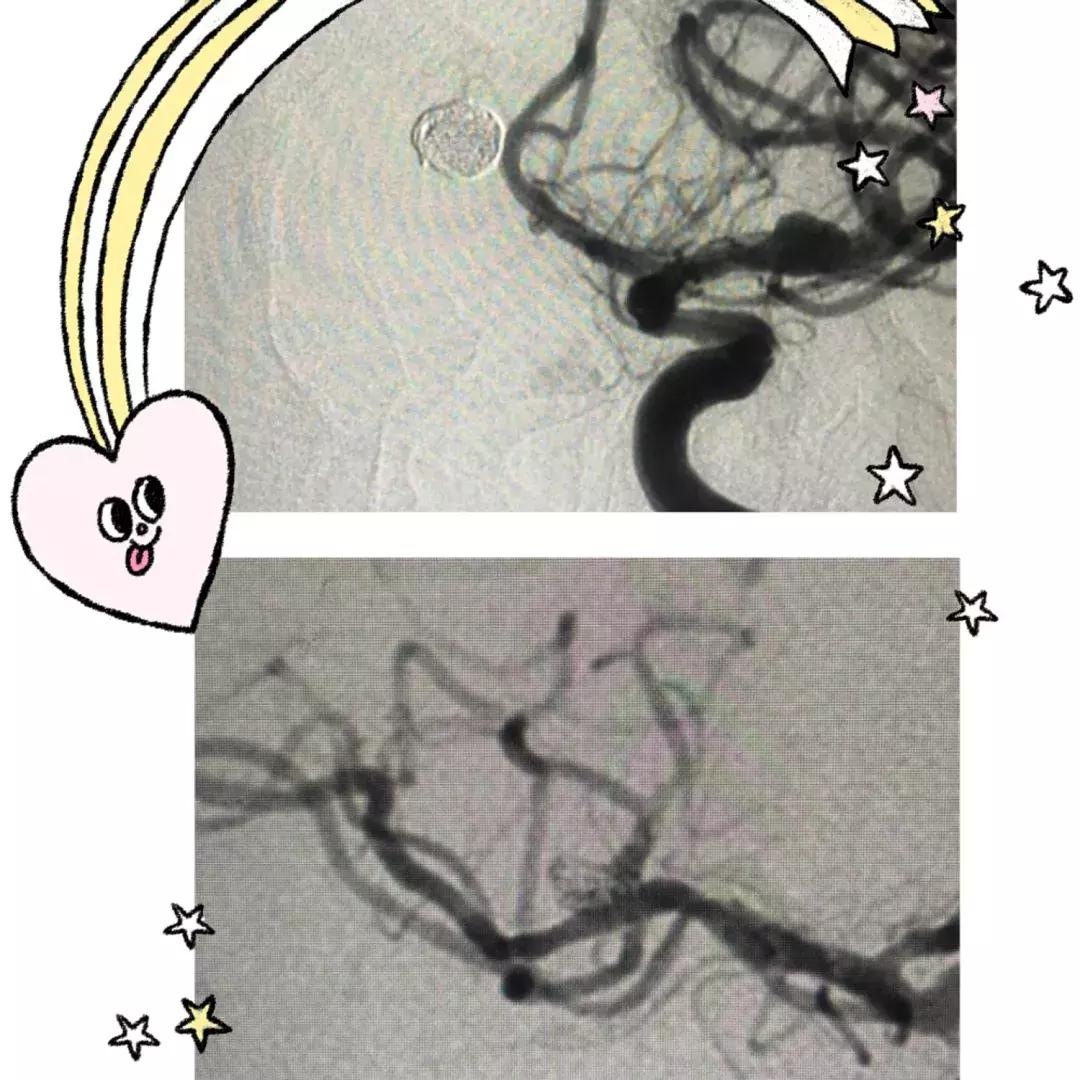

左侧大脑前动脉前交通动脉瘤,瘤颈8.1mm,瘤体8.1mmx3.3mm,右侧大脑中动脉上下干分叉处动脉瘤,瘤颈5.1mm,瘤体5.1mmx4.7mm毫米。均在路图导引下,经支架导管引入支架至动脉瘤颈处,支架半释放,在导丝配合下,将微导管送入动脉瘤腔内,撤出微导丝,依次填塞弹簧圈至瘤腔腔内,完全释放支架,术后反复造影,提示动脉瘤栓塞致密,无造影剂滞留。该次手术一次性解决了两个瘤体破裂的风险!